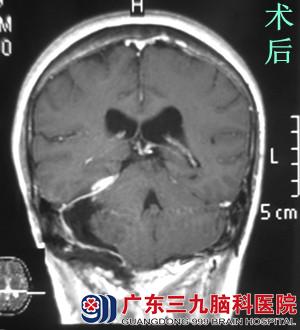

刚放暑假,易老师就被儿女催着去检查,结果当地医院行头颅CT检查后,提示右侧桥小脑角后部占位,易老师想着健康体检还真是不能忽视。为进一步明确病情,易老师来到广东三九脑科医院行头颅MR检查,提示:右侧小脑天幕示一较大的团块状占位性病变,大小约6.37*4.37*5.65cm,相邻脑组织明显受推压。完善相关检查后,由综合神经外科(神经外五科)鲁明主任主刀,在全麻下行右侧后颅窝巨大脑膜瘤切除术,术中显微镜下见灰白色肿瘤组织,质中,予超声刀分块切除,肿瘤侵犯横窦,在显微镜下全切肿瘤,手术顺利结束。术后易老师很快清醒,无任何的功能障碍,经过专科治疗护理,康复出院。术后病理结果:过渡型脑膜瘤(WHO I级)。